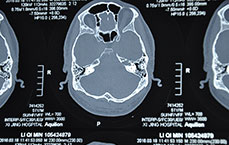

在耳鼻咽喉疾病微创治疗技术方面有着深入研究,成绩斐然,得到业内医生的高度评价。擅长治疗鼻炎、鼻窦炎等耳鼻喉常见病及疑难疾病,特别擅长中西结合治疗耳鸣、突发性耳聋、神经性耳聋等疾病,在中耳炎等其它疑难病症上见解独到…【详情】

冯亮主任答:目前运用中西结合治疗效果明显。1:采用糖皮质治疗。因为它有这个抗炎、降低免疫反应,同时减少内耳血管内皮细胞的水肿,它对治疗的疗效是肯定的。2:第二类就是采用抗凝和降纤的治疗方法,因突发性耳聋的病人,他血中的纤维蛋白原在增高,血粘稠度在增高,那么我们就要用一些药来溶这个酸或是降纤的,改善局部微循环。3:第三类就是采用营养、刺激神经和毛细胞的治疗方法,比如耳模+针灸,听神经定位治疗等…【详情】